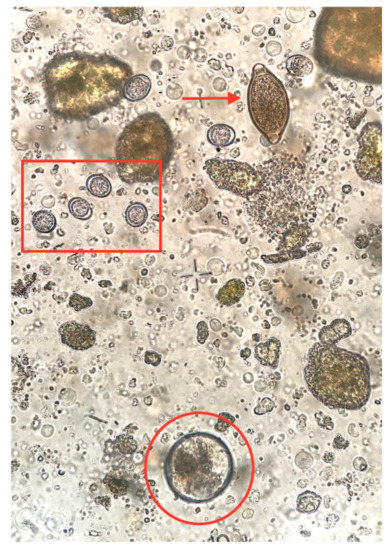

4.2. Coprological Methods Used